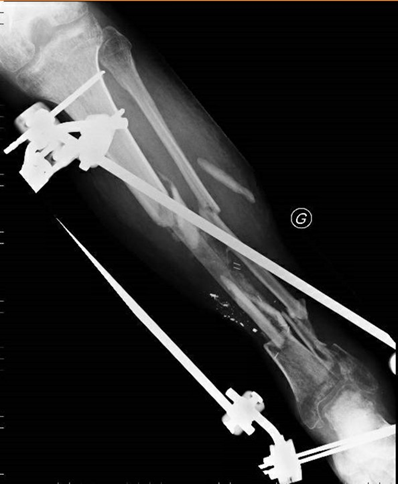

Figure 11, 12 : Our final choice was for a contralateral tibial rod.

Operative technique

The graft was implanted centromedullary to fill the gap between the two tibial extremities, bridging the loss of substance in addition of spongy grafts. The two surgical approaches were closed by simple suture.

Figure 13 : The original fixator was kept in place for the necessary time with no local complications.